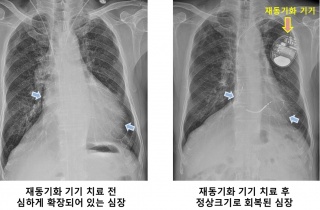

»ï¼º¼­¿ï, ±¹³» ÃÖÃÊ ½ÉÀåÀ絿±âÈ­Ä¡·á 300·Ê ´Þ¼º

[µ¥Àϸ®¸Þµð ¹Ú¼ºÀº ±âÀÚ] »ï¼º¼­¿ïº´¿ø(¿øÀå ±Ç¿ÀÁ¤)Àº ½ÉÀå³úÇ÷°üº´¿ø ºÎÁ¤¸Æ¼¾ÅÍ¿¡¼­ ±¹³» óÀ½À¸·Î ½ÉÀåÀ絿±âÈ­Ä¡·á 300·Ê2020-05-07 11:50:17